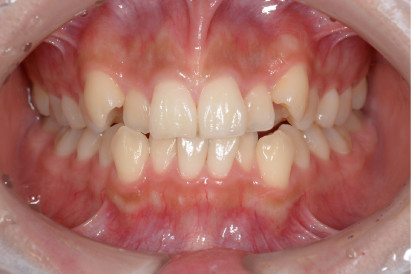

• 症例6

術前

*

術後

年代、性別

40代、女性

職業

会社員

主訴

歯並び相談

部位

インビザラインによる部分矯正

治療期間

6ヶ月

矯正費用

45万円

施術説明

矯正治療を長年希望していましたが、費用的に躊躇していたそうですが、審査の結果インビザラインの部分矯正で起用を抑えて対応できると判断しました。半年の治療期間で希望通りの結果を出す事ができ喜んで頂きました。

副作用・リスク

なし